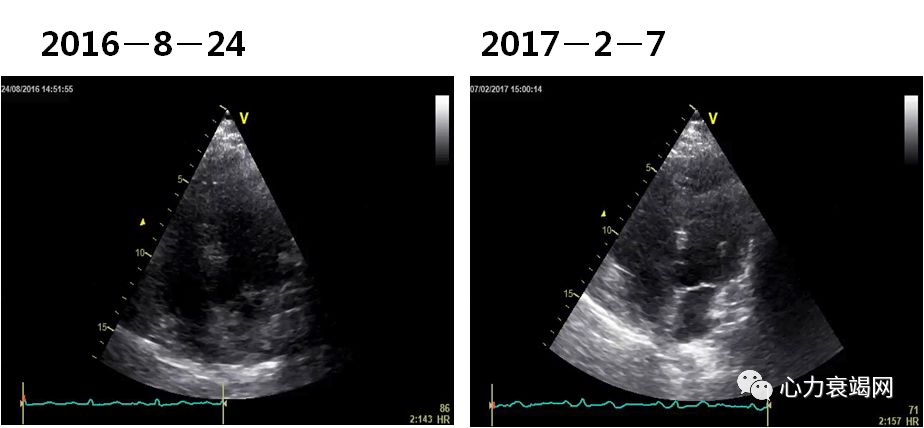

➤ 患者,AJP, 男性,75岁,高加索人

➤ 入院时间:2016.1.7

2016-1-11NT-proBNP 9950ng/ml

➤ 入院后予抗感染治疗,加强利尿,气急症状好转。

➤ 出院带药:

雷米普利 5mg qd

琥珀酸美托洛尔 47.5mg qd

呋塞米 40mg qd

螺内酯 20mg qd